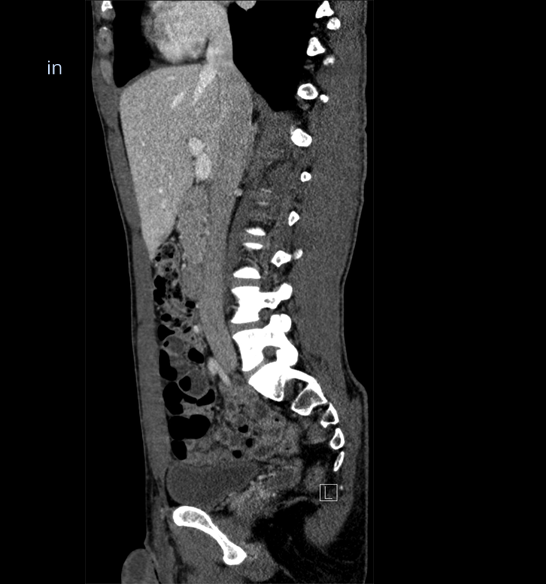

Body

Covers abdominal CT anatomy.